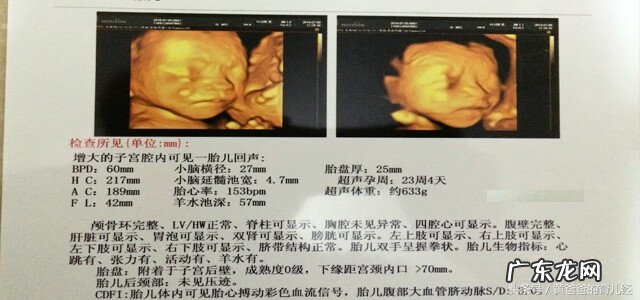

四、第四次彩超是在第23周4天,是四维彩超检查 。

【彩超怎么看胎儿性别 彩超看胎儿性别图解】这时从图中就可以清晰看出宝宝的头部、手、脚等其他部位了 。再次证明胎心率高于140是生女孩是不准确的 。最后医生还说一句,很像你,这个难道是暗示我,是男宝宝呢?因为当时不知道,所以心中笑了一下,果然我的是生男孩 。